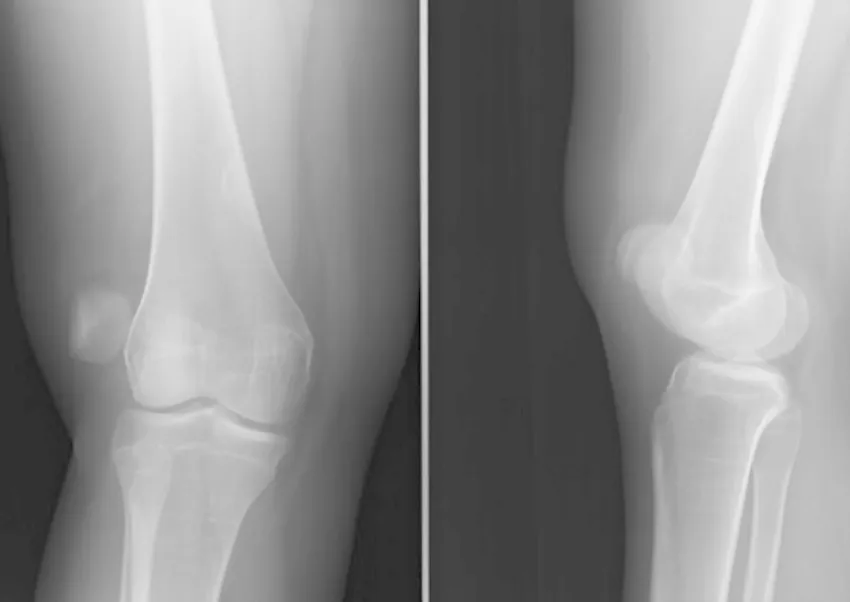

جابجایی کشکک زانو (Patellar Dislocation) یکی از آسیبهای شایع زانو است که معمولاً بر اثر ضربه مستقیم، پیچخوردگی ناگهانی یا حرکت نادرست رخ میدهد. در این حالت، کشکک که باید در شیار مخصوص خود حرکت کند، از جای طبیعیاش خارج میشود و باعث درد شدید، تورم و محدودیت حرکتی میگردد. هرچند در بعضی موارد کشکک بهطور خودبهخود به جای خود بازمیگردد، اما همچنان معاینه پزشکی ضروری است، زیرا ممکن است آسیبهای دیگری مانند پارگی رباطها یا صدمه به غضروف نیز رخ داده باشد. شناخت علائم، علتها و روشهای درمان این مشکل میتواند به بهبود سریعتر و جلوگیری از آسیبهای مکرر کمک کند.

جابجایی کشکک زانو یا Patellar Dislocation حالتی است که در آن کشکک (استخوان کوچک جلوی زانو) از شیار طبیعی خود در انتهای استخوان ران (Femur) خارج میشود. در حالت طبیعی، کشکک هنگام خم و راست کردن پا در یک شیار عمودی به نام شیار تروکلئار حرکت میکند و توسط رباطها و تاندونها در جای خود نگه داشته میشود. اما در زمان ضربه ناگهانی، پیچش شدید یا فشار غیرعادی، کشکک به ویژه به سمت بیرون زانو (لترال) جابهجا میشود.

نکته مهم: تصمیمگیری برای جراحی باید پس از بررسی کامل معاینه بالینی، تصویربرداری (MRI یا سیتی اسکن) و ارزیابی شرایط فردی صورت گیرد. هدف، بازگرداندن عملکرد طبیعی زانو و جلوگیری از دررفتگیهای مکرر است.